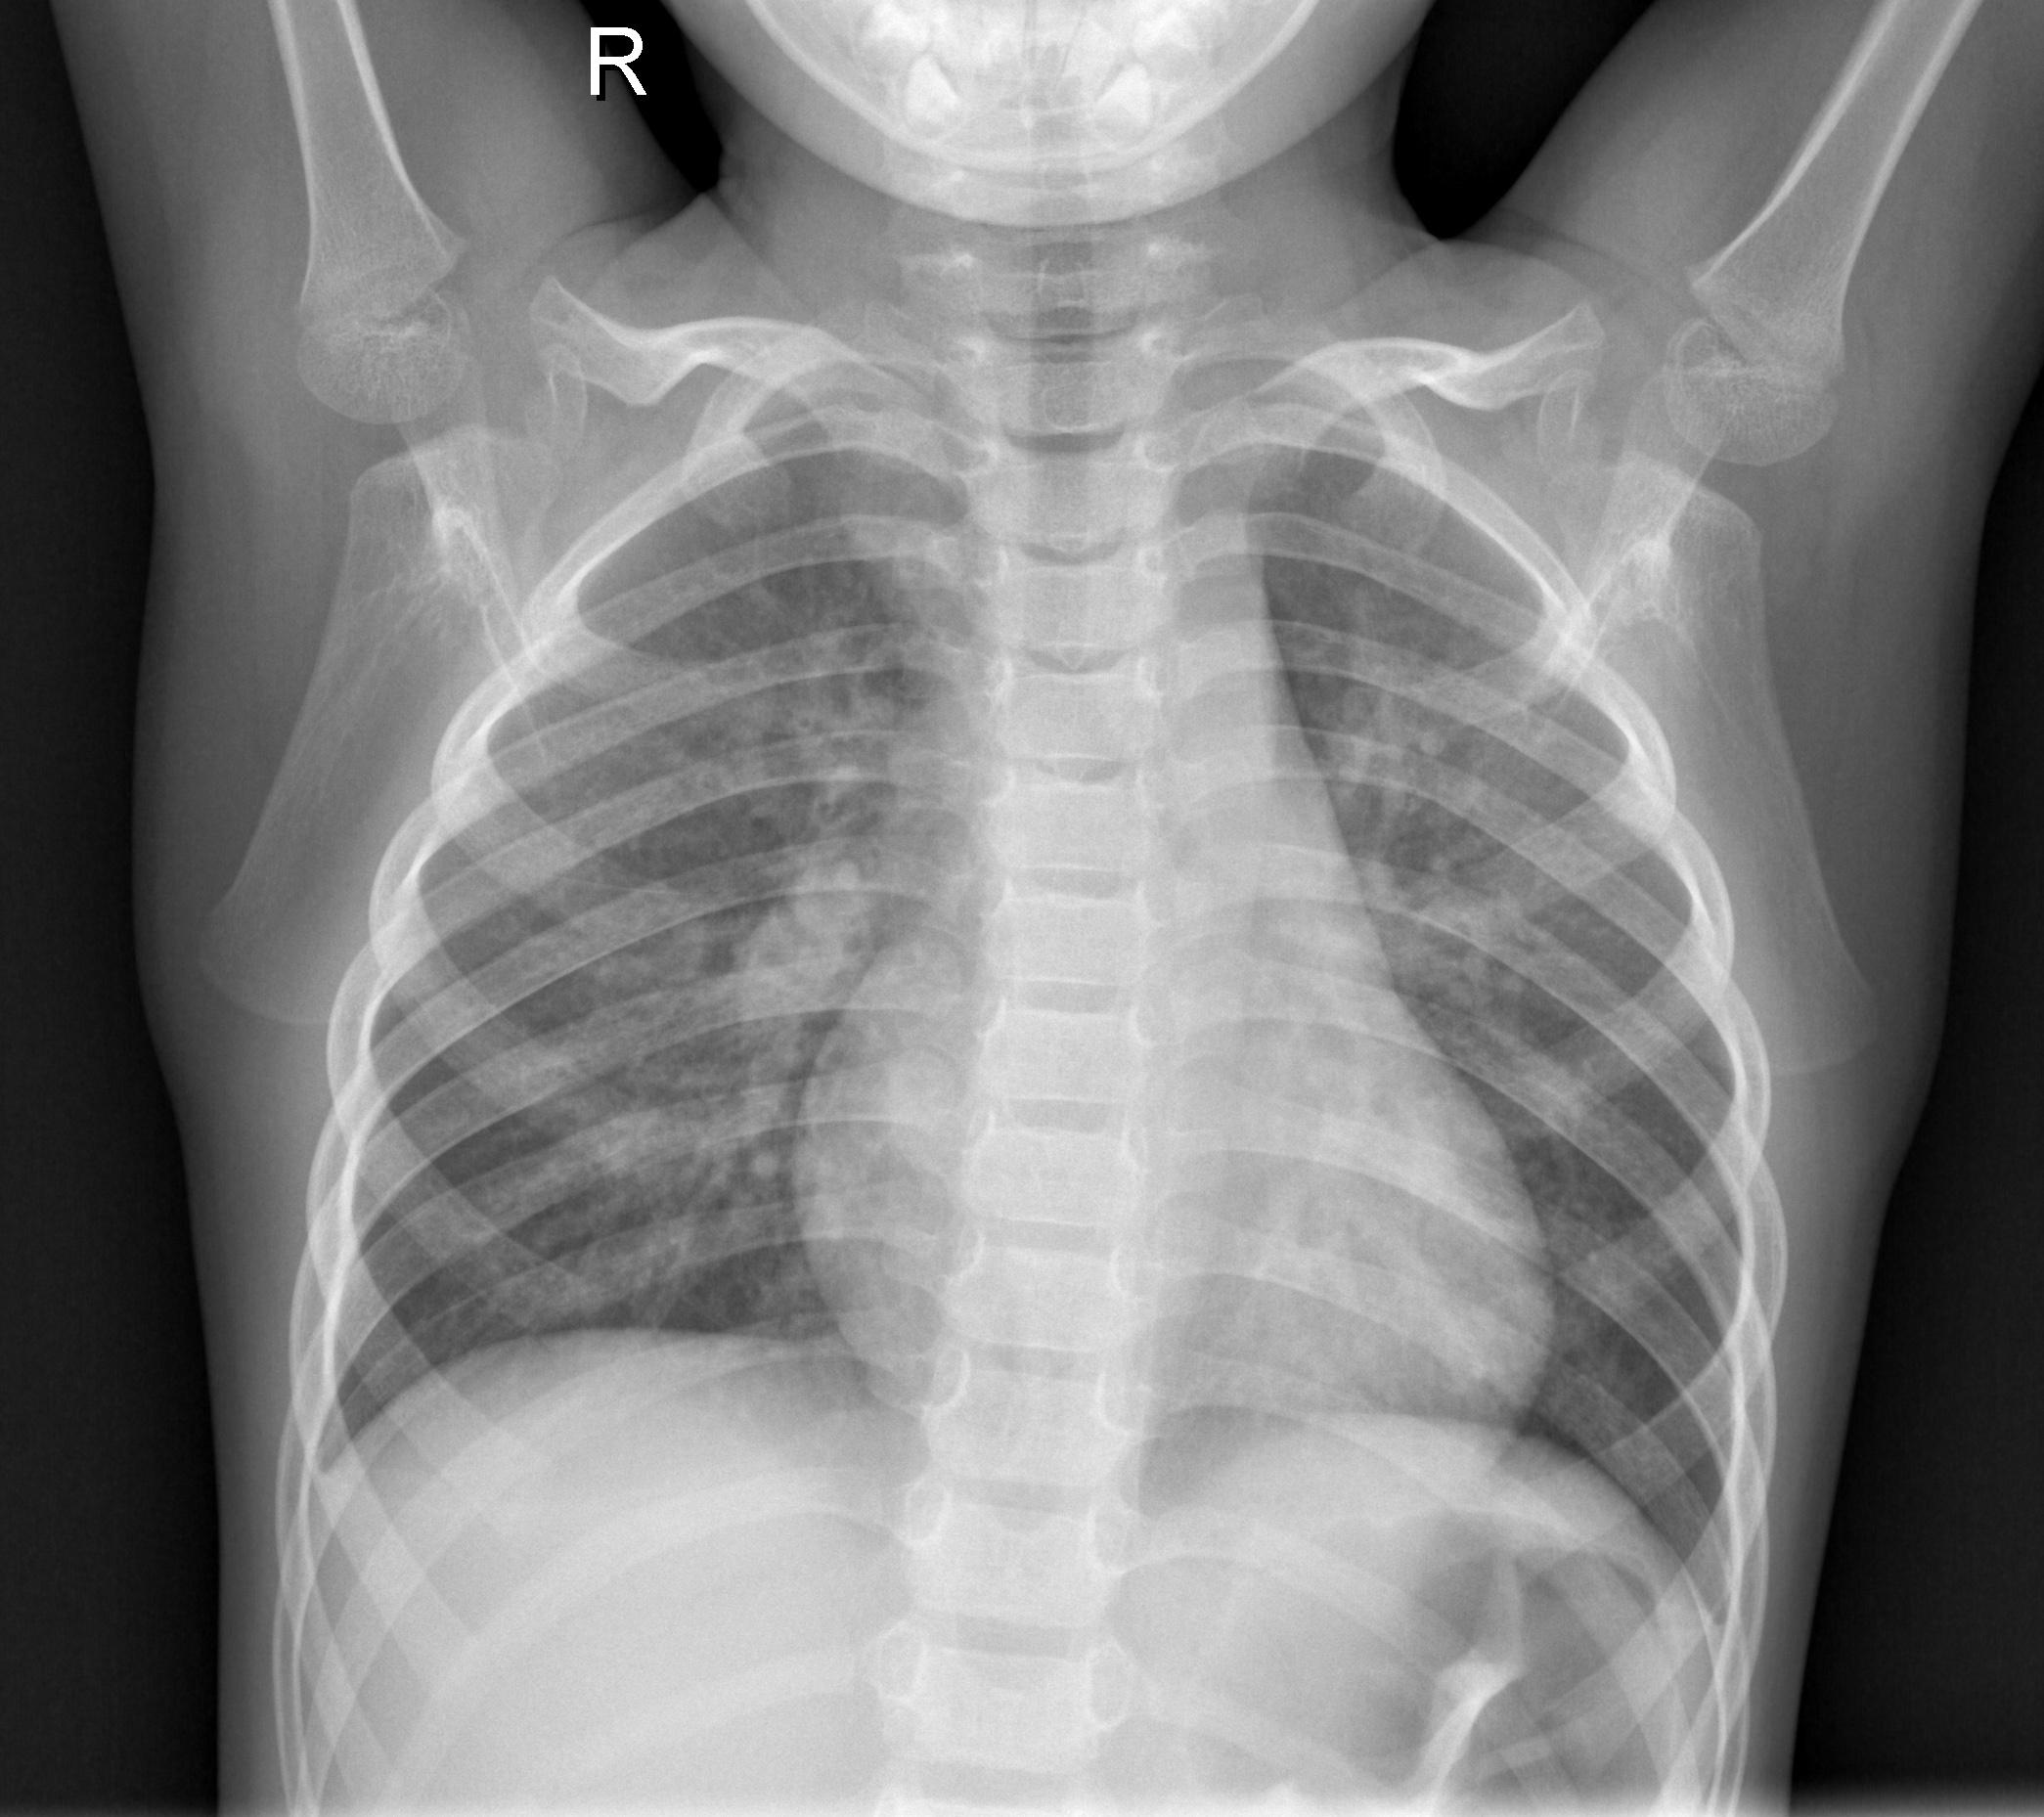

I was inspired to develop this image diagnostic tool by the significant challenge posed by the misclassification of chest X-ray images depicting diseases like Pneumonia, Tuberculosis, and Breast Cancer. I aimed to address the problem of delayed intervention, compromised patient outcomes, and the high cost associated with accurate interpretations, particularly in resource-constrained regions.

The image diagnostic tool leverages Convolutional Neural Networks (CNNs) and deep learning techniques to analyze and classify chest X-ray images. By utilizing transfer learning and the VGG19 CNN architecture, the tool aids doctors in accurately interpreting these images, reducing the number of false positives and negatives. It provides a collaborative approach where doctors can upload the images, and the tool provides an initial diagnosis that is verified by the doctor based on their medical expertise.

I trained CNN models using deep learning techniques to build the image diagnostic tool. I employed transfer learning and utilized the VGG19 CNN architecture. I trained the models on a large dataset of chest X-ray images depicting Pneumonia, Tuberculosis, and Breast Cancer. I developed the tool with a user-friendly interface for doctors to upload images and receive timely and accurate diagnoses.